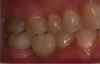

Fig. 9 through Fig. 11 The implant shifted slightly to mesial to avoid buccal concavity and bone graft. The implant was placed with a guide and a tissue punch was done, negating a flap. Figure 11 is the immediate postoperative photograph.

Figure 9

Figure 10

Figure 11